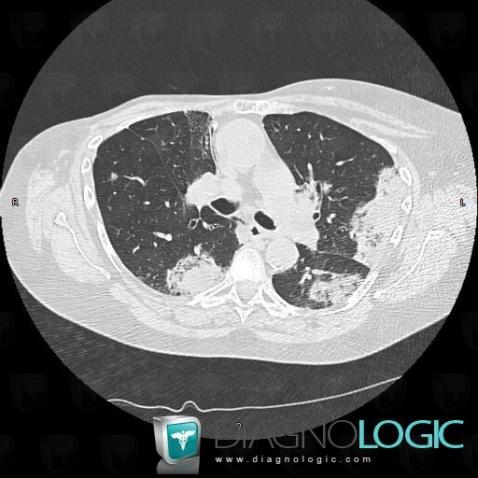

Bronchioloalveolar carcinoma, Pulmonary parenchyma, CT

Here is the specific information in the key image above:

- Diagnosis Bronchioloalveolar carcinoma, Location(s) Pulmonary parenchyma, with gamuts Chronic consolidation, Localized consolidation